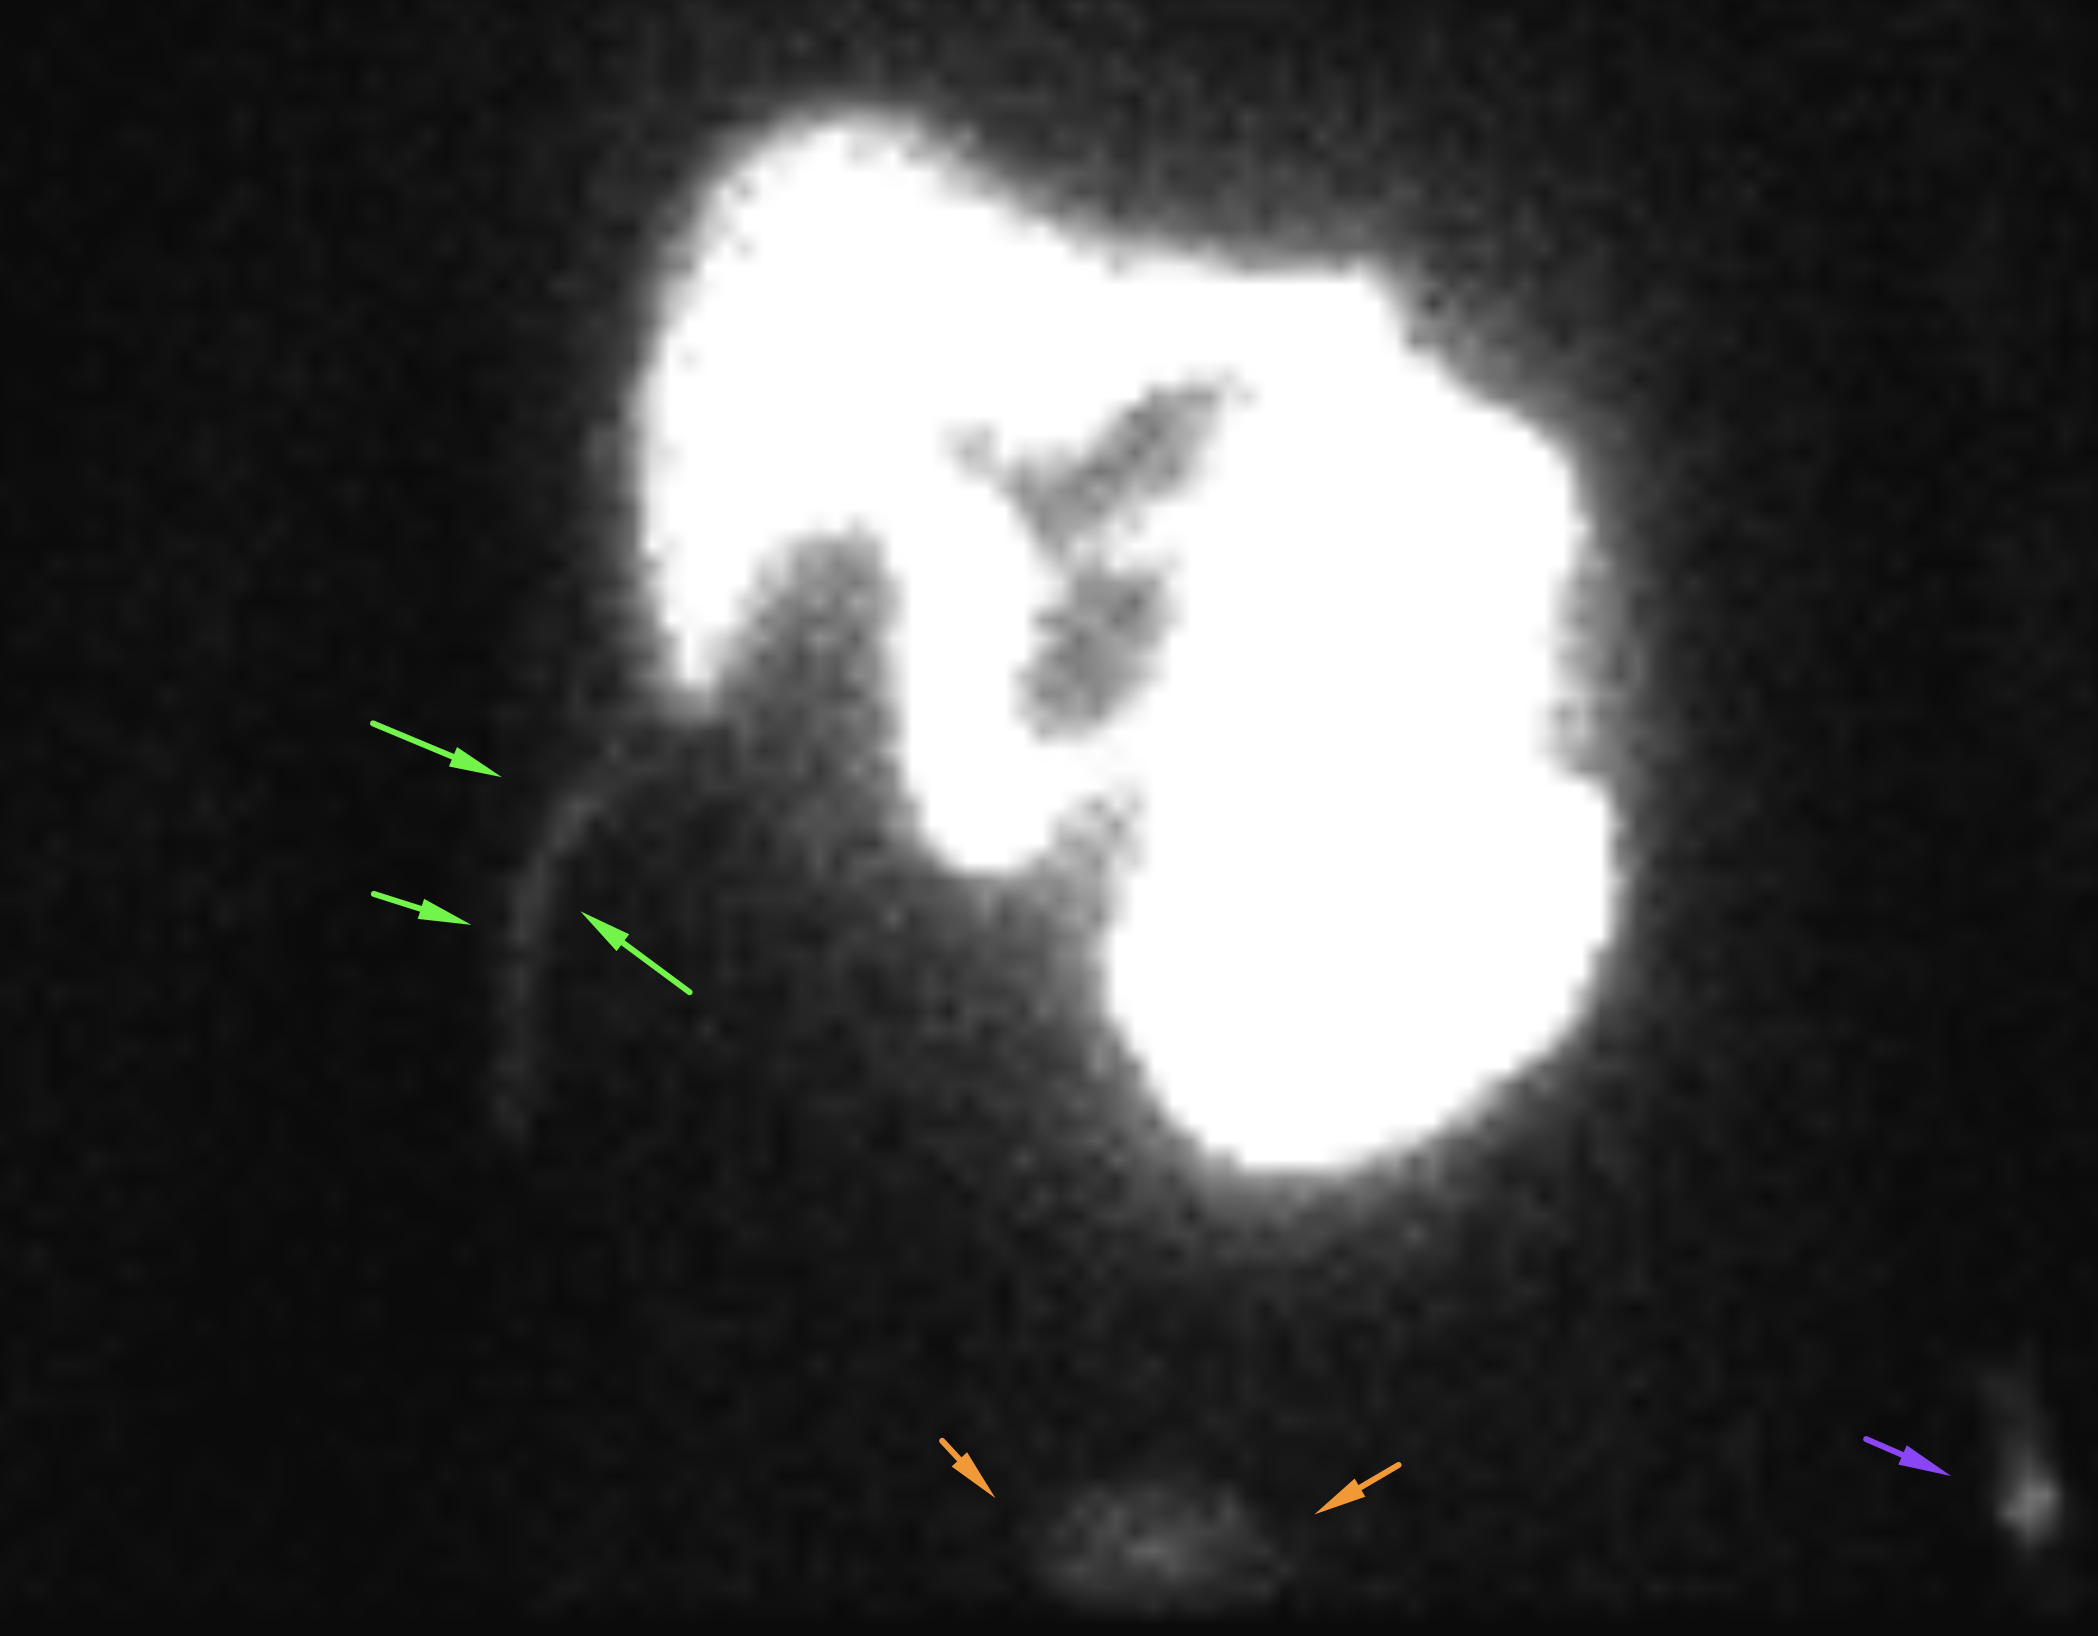

Age: 84

Sex: Male

Indication: Left-sided chest pain, recent cholecystectomy

Radiotracer: Tc99m mebrofenin (an iminodiacetic acid analog)

Sample ReportPositive for biliary leak, which is drained by the existing surgical drains.

No evidence of intra-abdominal bile collections.

No evidence of common bile duct obstruction.